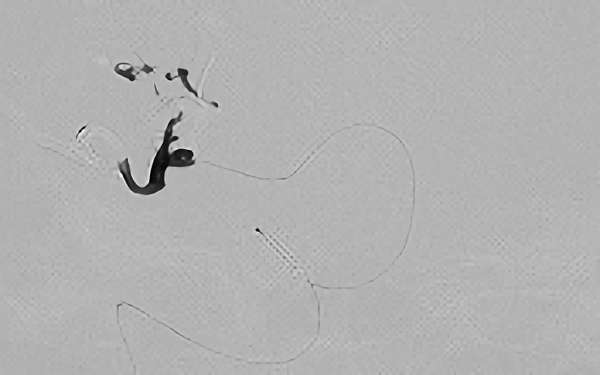

'24年8月

左前頭葉脳動静脈奇形

10代

秋田県の病院

No.1494 手術中